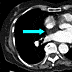

Fusion image between the axial transmission image (used for attenuation correction of PET images) and the axial emission FDG-PET image in Figure 10 confirms the interatrial septal location of the intense FDG uptake (blue arrow). Physiologic left ventricular myocardial FDG uptake is noted (black arrows). The transmission and emission images were acquired at the same level and the same bed position.